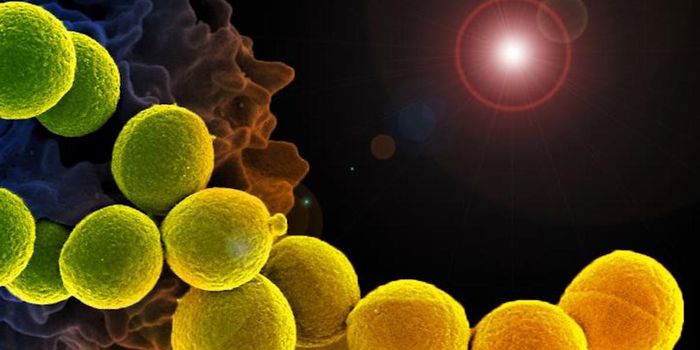

SEP 17, 2021Cell & Molecular BiologyMRSA (methicillin-resistant Staphylococcus aureus) is a well known superbug, a pathogenic microbe that can cause serious ...